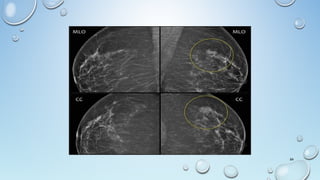

MASS

A 'Mass' is a space occupying 3D lesion seen in two different

projections.

If a potential mass is seen in only a single projection it should be called

a 'asymmetry' until its three-dimensionality is confirmed.

Shape: oval (may include 2 or 3 lobulations), round or irregular

Margins: circumscribed, obscured, microlobulated, indistinct,

spiculated

Density: high, equal, low or fat-containing.